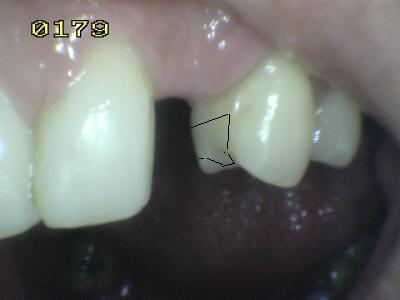

Vista vestibular. El matiz del póntico (flecha verde) se determino con el primer premolar (flecha marrón) Antes del tratamiento